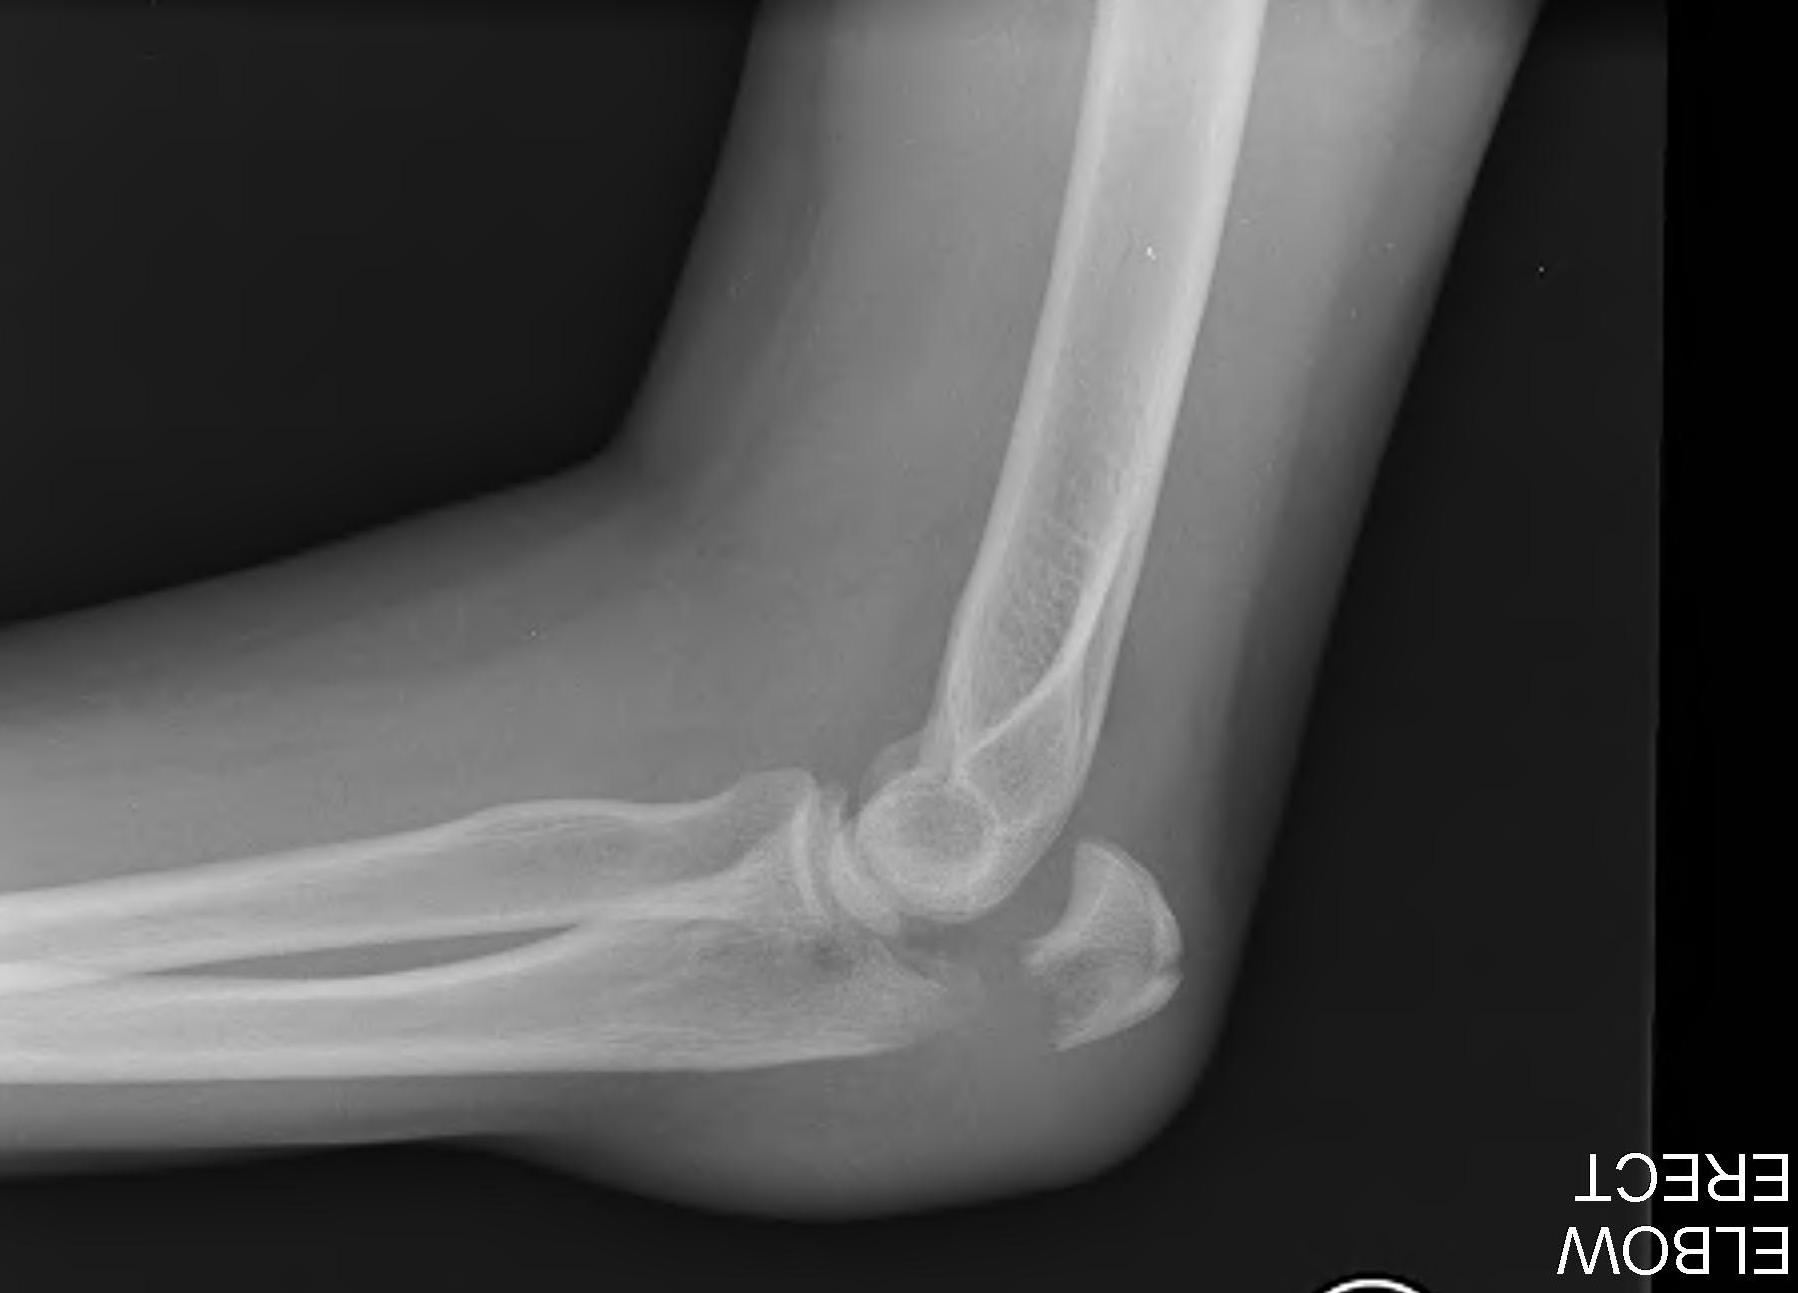

Proximal articular portion of the ulna

- greater sigmoid notch articulates with trochlea

- has a central bare area

- flexion / extension

Triceps insertion

- attaches to olecranon

- displaces olecranon fragment superiorly